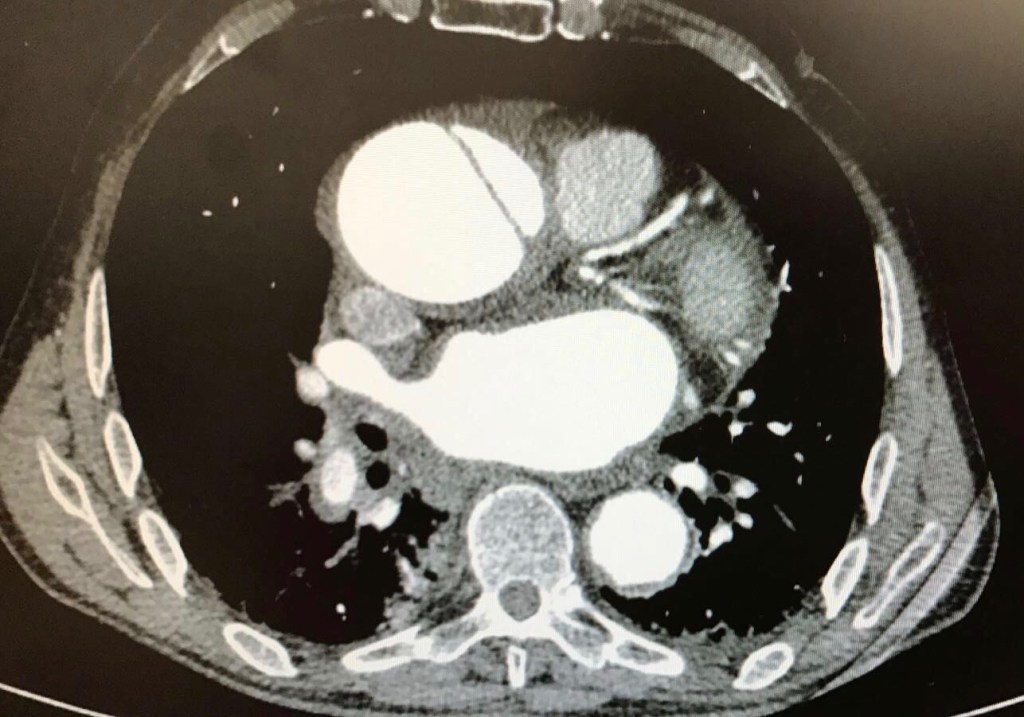

Disección aórtica aguda

La disección de aorta está causada por la rotura de una de las capas internas de la pared del vaso, lo que hace que la sangre penetre en la misma creando dos luces (la luz verdadera y la falsa), con el consiguiente riesgo de rotura. Es una enfermedad tremendamente grave que requiere tratamiento médico y quirúrgico emergente. Si no es así, la mortalidad es altísima y aumenta un 1% por hora que se espere.

El tratamiento quirúrgico constituye uno de los mayores retos para los cirujanos cardiovasculares y está indicado en todas las disecciones en las que se afecta la raíz aórtica o la aorta ascendente, así como en caso de rotura. El objetivo es sustituir la zona por la que la sangre entra en la pared, así como la mayor parte de la aorta enferma posible. En ocasiones, es necesario reeemplazar también la válvula aórtica, ya que puede ser «insuficiente» (los velos no coaptan bien). Las técnicas que se emplean son algunas de las anteriormente descritas para los aneurismas, con la salvedad de que el riesgo de hemorragia es mayor.